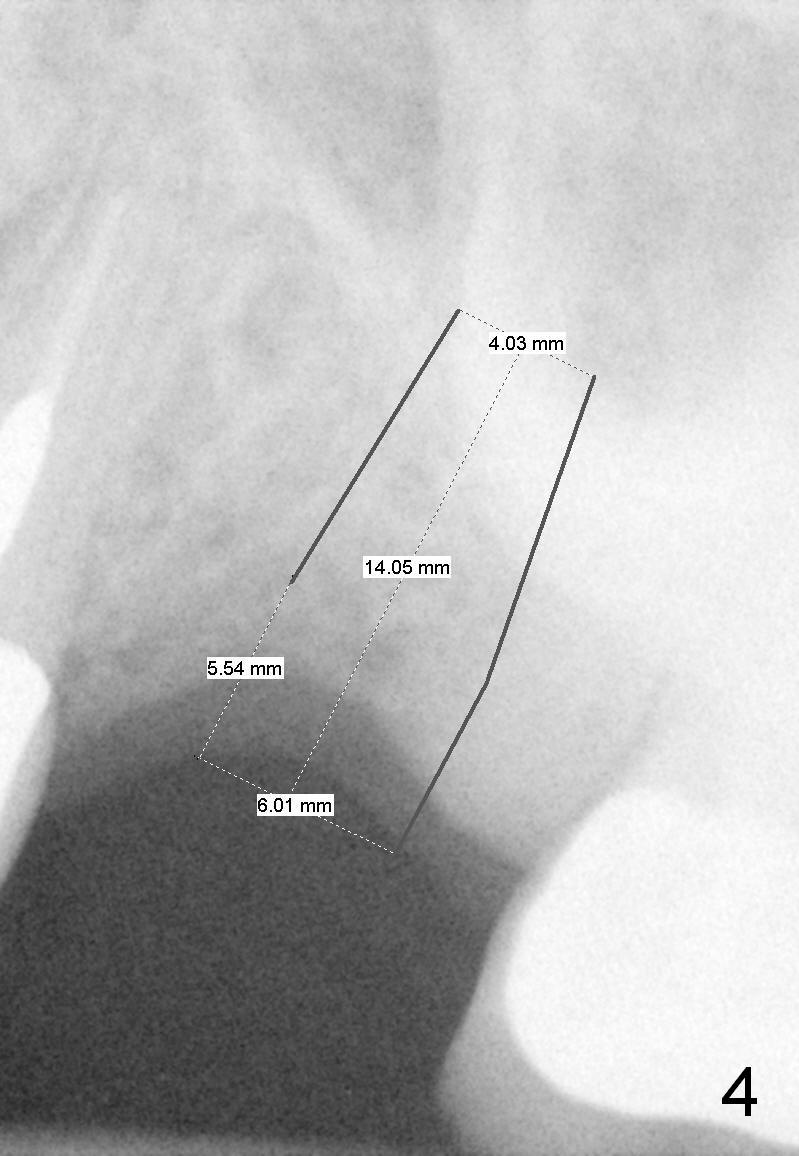

She suddenly decides to have an implant to be placed at the site of #31, 5.5 years post extraction (Fig.5). If she does not have chance to take preop CT, the initial osteotomy depth will be 8 mm. Then take the 1st intraop PA for bone height confirmation. If the bone height is <8 mm, use Master Sinus Lift Kit and SM Extra Wide Kit. Place an implant as low as possible, since the opposing tooth must have been supraerupted.